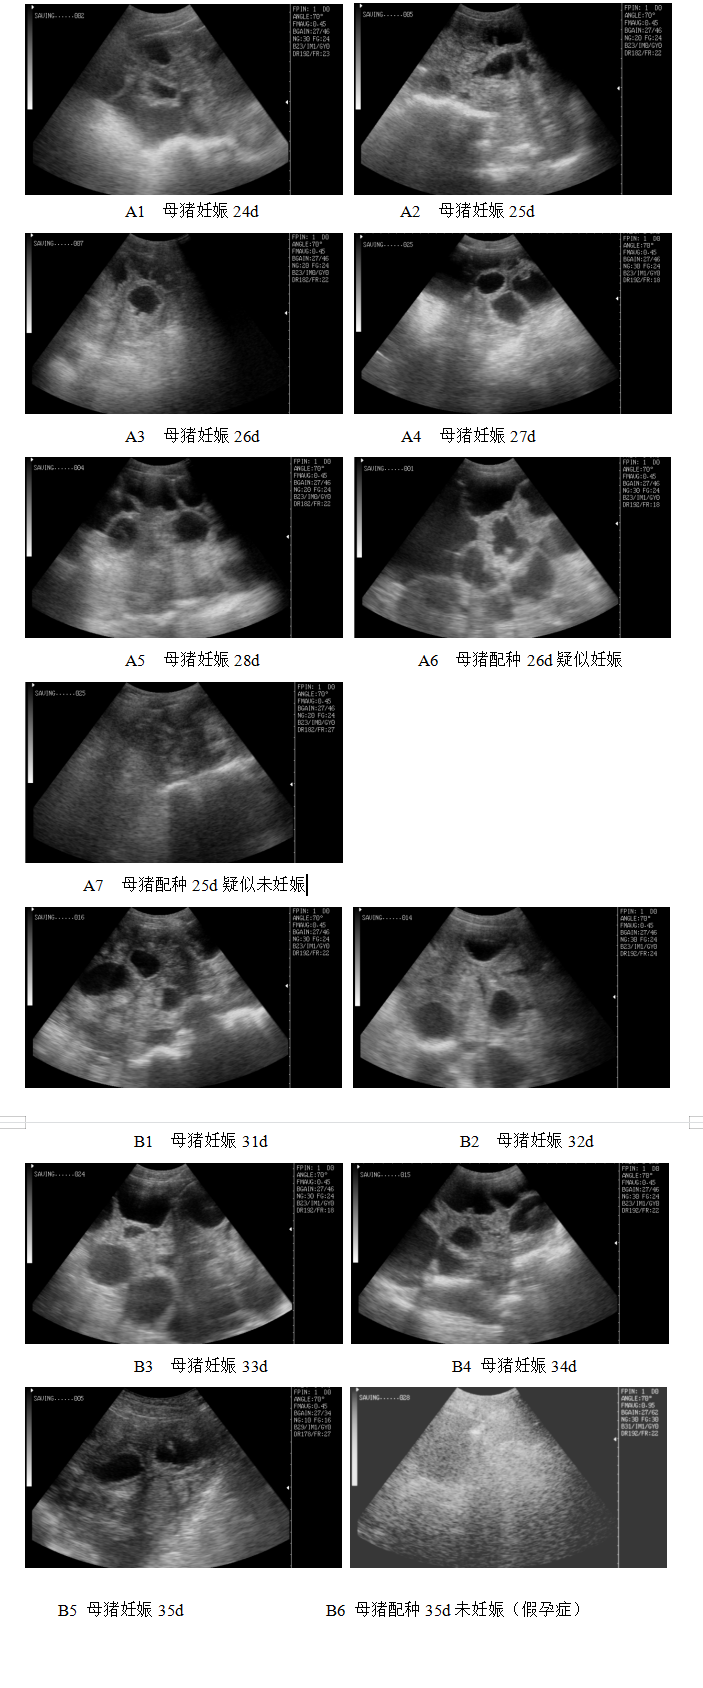

技术描述:(一)技术基本情况 妊娠诊断技术是减少猪场非生产天数、提高母猪繁殖效率的一项重要手段。常见的母猪早期妊娠诊断方法有公猪试...